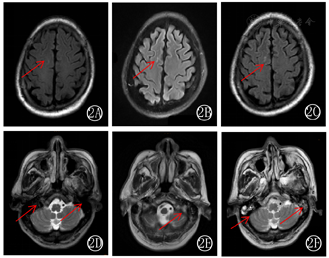

第3天,颅脑MR平扫双侧基底节、双侧额顶叶内见多发斑点状略长T1、略长T2信号,FLAIR序列呈略高信号,双侧乳突未见明显异常(图2)。第5天,行纯音听阈测定结果显示双耳为混合性聋,考虑急性感染、炎症导致听神经损伤(图3A)。第6天,未再发热,意识模糊稍减轻,复查脑脊液示总蛋白2.07 g/L,葡萄糖3.36 mmol/L,氯化物119.7 mmol/L;有核细胞计数620×106/L,中性粒细胞占比0.3,淋巴细胞69%,单核细胞1%(图1)。第10天,脑脊液nGS回报猪链球菌(序列数1889,相对丰度93.27%),请临床药师会诊:患者有生肉类接触史,不排除在处理过程中皮肤黏膜有破损细菌入血可能,结合早期发热、意识模糊症状,脑脊液感染象,考虑猪链球菌为致病菌,猪链球菌脑膜脑炎诊断明确。

两耳侧及枕部疼痛、发胀明显,复查脑MRI:双侧基底节、额、顶叶内见多发斑点、片状略长T1、略长T2信号,FLAIR序列呈略高信号,左侧乳突见长T2信号,考虑感染猪链球菌导致特征性症状及神经系改变相关(图2)。第11天,血常规白细胞计数10.87×109/L(表1)。第15天患者右踝关节红肿热痛,经手足外科会诊:猪链球菌感染可引起败血症、关节炎、心内膜炎等,考虑与原发感染有关,建议留取血培养及药敏。第20天,脑脊液及血培养均回报阴性。右踝关节仍有红肿疼痛,右踝关节正侧位未见骨折、脱位。下肢血管彩超:右侧胫后静脉及右侧小腿肌间静脉血栓形成。第34天,患者仍有头晕、耳聋、耳鸣,夜间有头痛。脑MRI:双侧基底节、放射冠、额顶叶内见多发斑点状略长T1、略长T2信号,FLAIR序列呈略高信号,双侧乳突见长T2信号,考虑猪链球菌感染累及听神经及前庭神经(图2)。第35天,患者右踝关节疼痛明显减轻,可下床站立,步态不稳,需搀扶。第42天,患者头痛、右踝关节疼痛减轻,精神状态可,耳聋、耳鸣无明显变化,复查脑脊液基因二代测序示猪链球菌(序列数3),脑脊液有葡萄糖、蛋白质、氯化物、核细胞计数等指标逐渐好转(图1)。血常规、C反应蛋白、血沉等感染指标好转(表1)。

猪链球菌脑膜脑炎临床症状明显,但缺乏特异性,脑脊液培养阳性率低,脑脊液宏基因组二代测序猪链球菌有助于早期诊断、识别。针对猪链球菌进行积极足剂量足疗程抗感染及综合治疗使患者病情逐渐好转。本例患者磁共振显示颅内白质异常信号,考虑与患者自身年龄、高血压等脑血管疾病相关性大,在抗菌药物全疗程并无明显差异性,可排除感染影响。在全疗程中,听力障碍持续进展是治疗的难点,在使用头孢曲松联合利奈唑胺抗感染基础上,配合足量地塞米松抗炎,可能是治疗猪链球菌中枢神经系统感染并发听力障碍患者的有效方法。而对于无法逆转的听力障碍,植入人工耳蜗,进行语言康复训练,或许能成为改善此类患者听力及生活质量的可行方法,为今后患者的治疗提供了新思路。但在猪链球菌感染治疗的整个过程中,需要患者本人和家属极大的耐心,才能帮助患者达到高效治愈的目标。